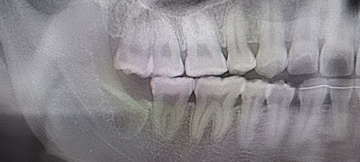

After(下親知らずの抜歯後) 横に生えた状態で埋まっている親知らずの抜歯後 虫歯がある親知らずの抜歯後 抜歯後の骨の状態のレントゲン像

1年後、取り除いた親知らず周囲の骨がしっかり再生したことを確認しました。